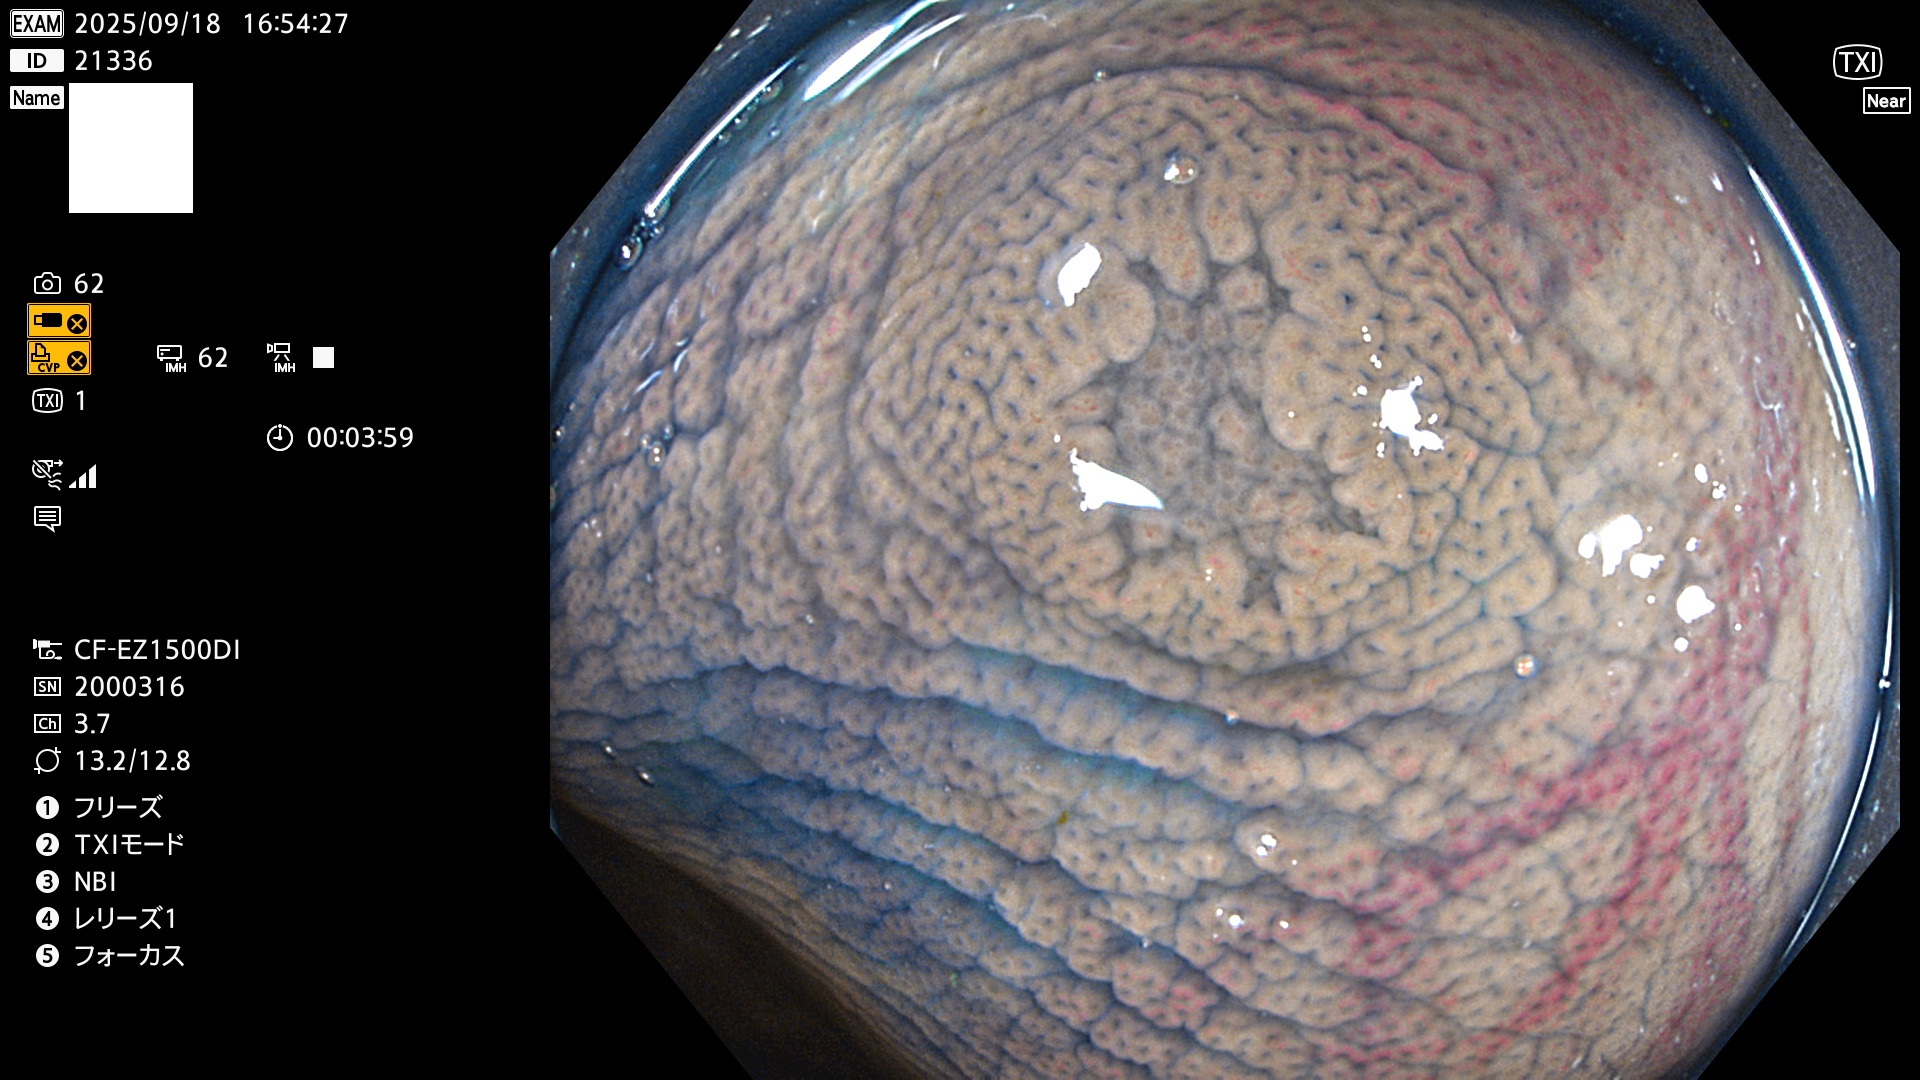

完全に平坦な物をUb、陥凹している物をUcと呼びます。Ubは認識が困難で、Ucはびらん(炎症)と紛らわしいために見落とされやすく、「内視鏡後・大腸癌」の原因になります。

専門的)Uc=De Novo癌? 内視鏡の解像度が低かった時代、このような説もありました。しかし今日の高精度内視鏡では良性の微小なUc型腺腫(APC遺伝子異常の腺腫)が日常的に見つかります。Ucこそが多段階発癌(Adenoma-Carcinoma Sequence)のMain Routeです。

毎週の検査(木・金・土・日)に発見されたUbとUc型・腺腫を、その週の日曜の夜にUPし1週間、提示します。

2025年9月17日〜9月21日の4日間(40件)6個 (Uc_ADR=6個/40人=15%)